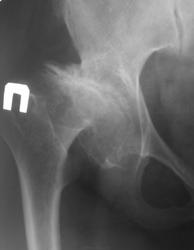

направительный диагноз двусторонний коксартроз. https://radiomed.ru/sites/default/files/styles/case_slider_image/public/user/5598/dsc_0352_0.jpg?itok=Aekj8yTf https://radiomed.ru/sites/default/files/styles/case_slider_image/public/user/5598/dsc_0351.jpg?itok=a9cFH23G ID:50940 Втр, 10/04/2012 - 21:28 #1 Гриша Хата Не на сайте Был на сайте: 10 лет 5 месяцев назад Зарегистрирован: 09.02.2011 - 20:40 Публикации: 665 Справа диспластический коксартроз, слева - диспластический неоартроз. Но это не должно быть новостью для больной. Ср, 11/04/2012 - 02:55 #2 Демчев Валентин... Не на сайте Был на сайте: 8 лет 1 неделя назад Зарегистрирован: 08.02.2011 - 15:40 Публикации: 445 Интересно почему раньше не прооперировали? Ср, 11/04/2012 - 21:08 #3 Александр Викторович Не на сайте Был на сайте: 8 лет 4 месяцев назад Зарегистрирован: 31.07.2010 - 13:05 Публикации: 639 Демчев Валентин Анатольевич wrote: Интересно почему раньше не прооперировали? не знаю, жительница другого района

Справа диспластический коксартроз, слева - диспластический неоартроз. Но это не должно быть новостью для больной.